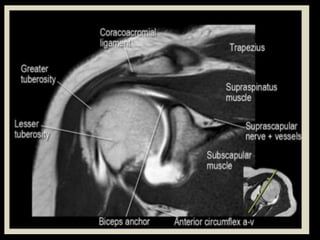

Hip Joint.

Shoulder

Joint.